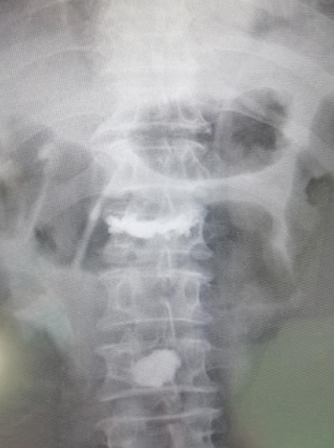

74岁老人骑电动车,被驶过的大货蹭倒,摔成腰1、腰3椎体压缩性骨折,接诊的betway在线登陆采用天玑骨科机器人精准“操刀”,为患者进行了椎体成形手术,24小时后老人已经下地活动,手术获得成功。

患者李大爷,家住丰县,被送到必威官方首页官网betway时,由脊柱科孟磊副主任医师接诊,老人腰1、腰3椎体压缩性骨折,这种压缩性骨折是无法通过普通的卧床静养就能自行恢复的,需要做椎体成形手术,脊柱科尚军主任和手术小组讨论后,决定采用骨科机器人辅助手术。